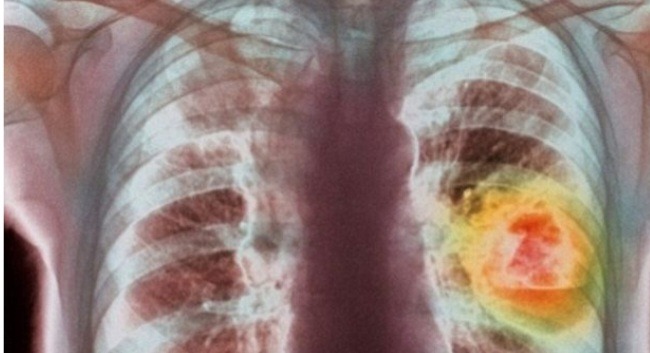

Por a mund të përmirësoni mushkëritë e zeza, të dëmtuara, për shkak të pirjes së duhanit? Është e mundur, por kërkon kohë dhe vendosmëri. Nëse keni pirë duhan për 20 vjet, mos prisni të shëroheni me disa muaj detoksifikimi.